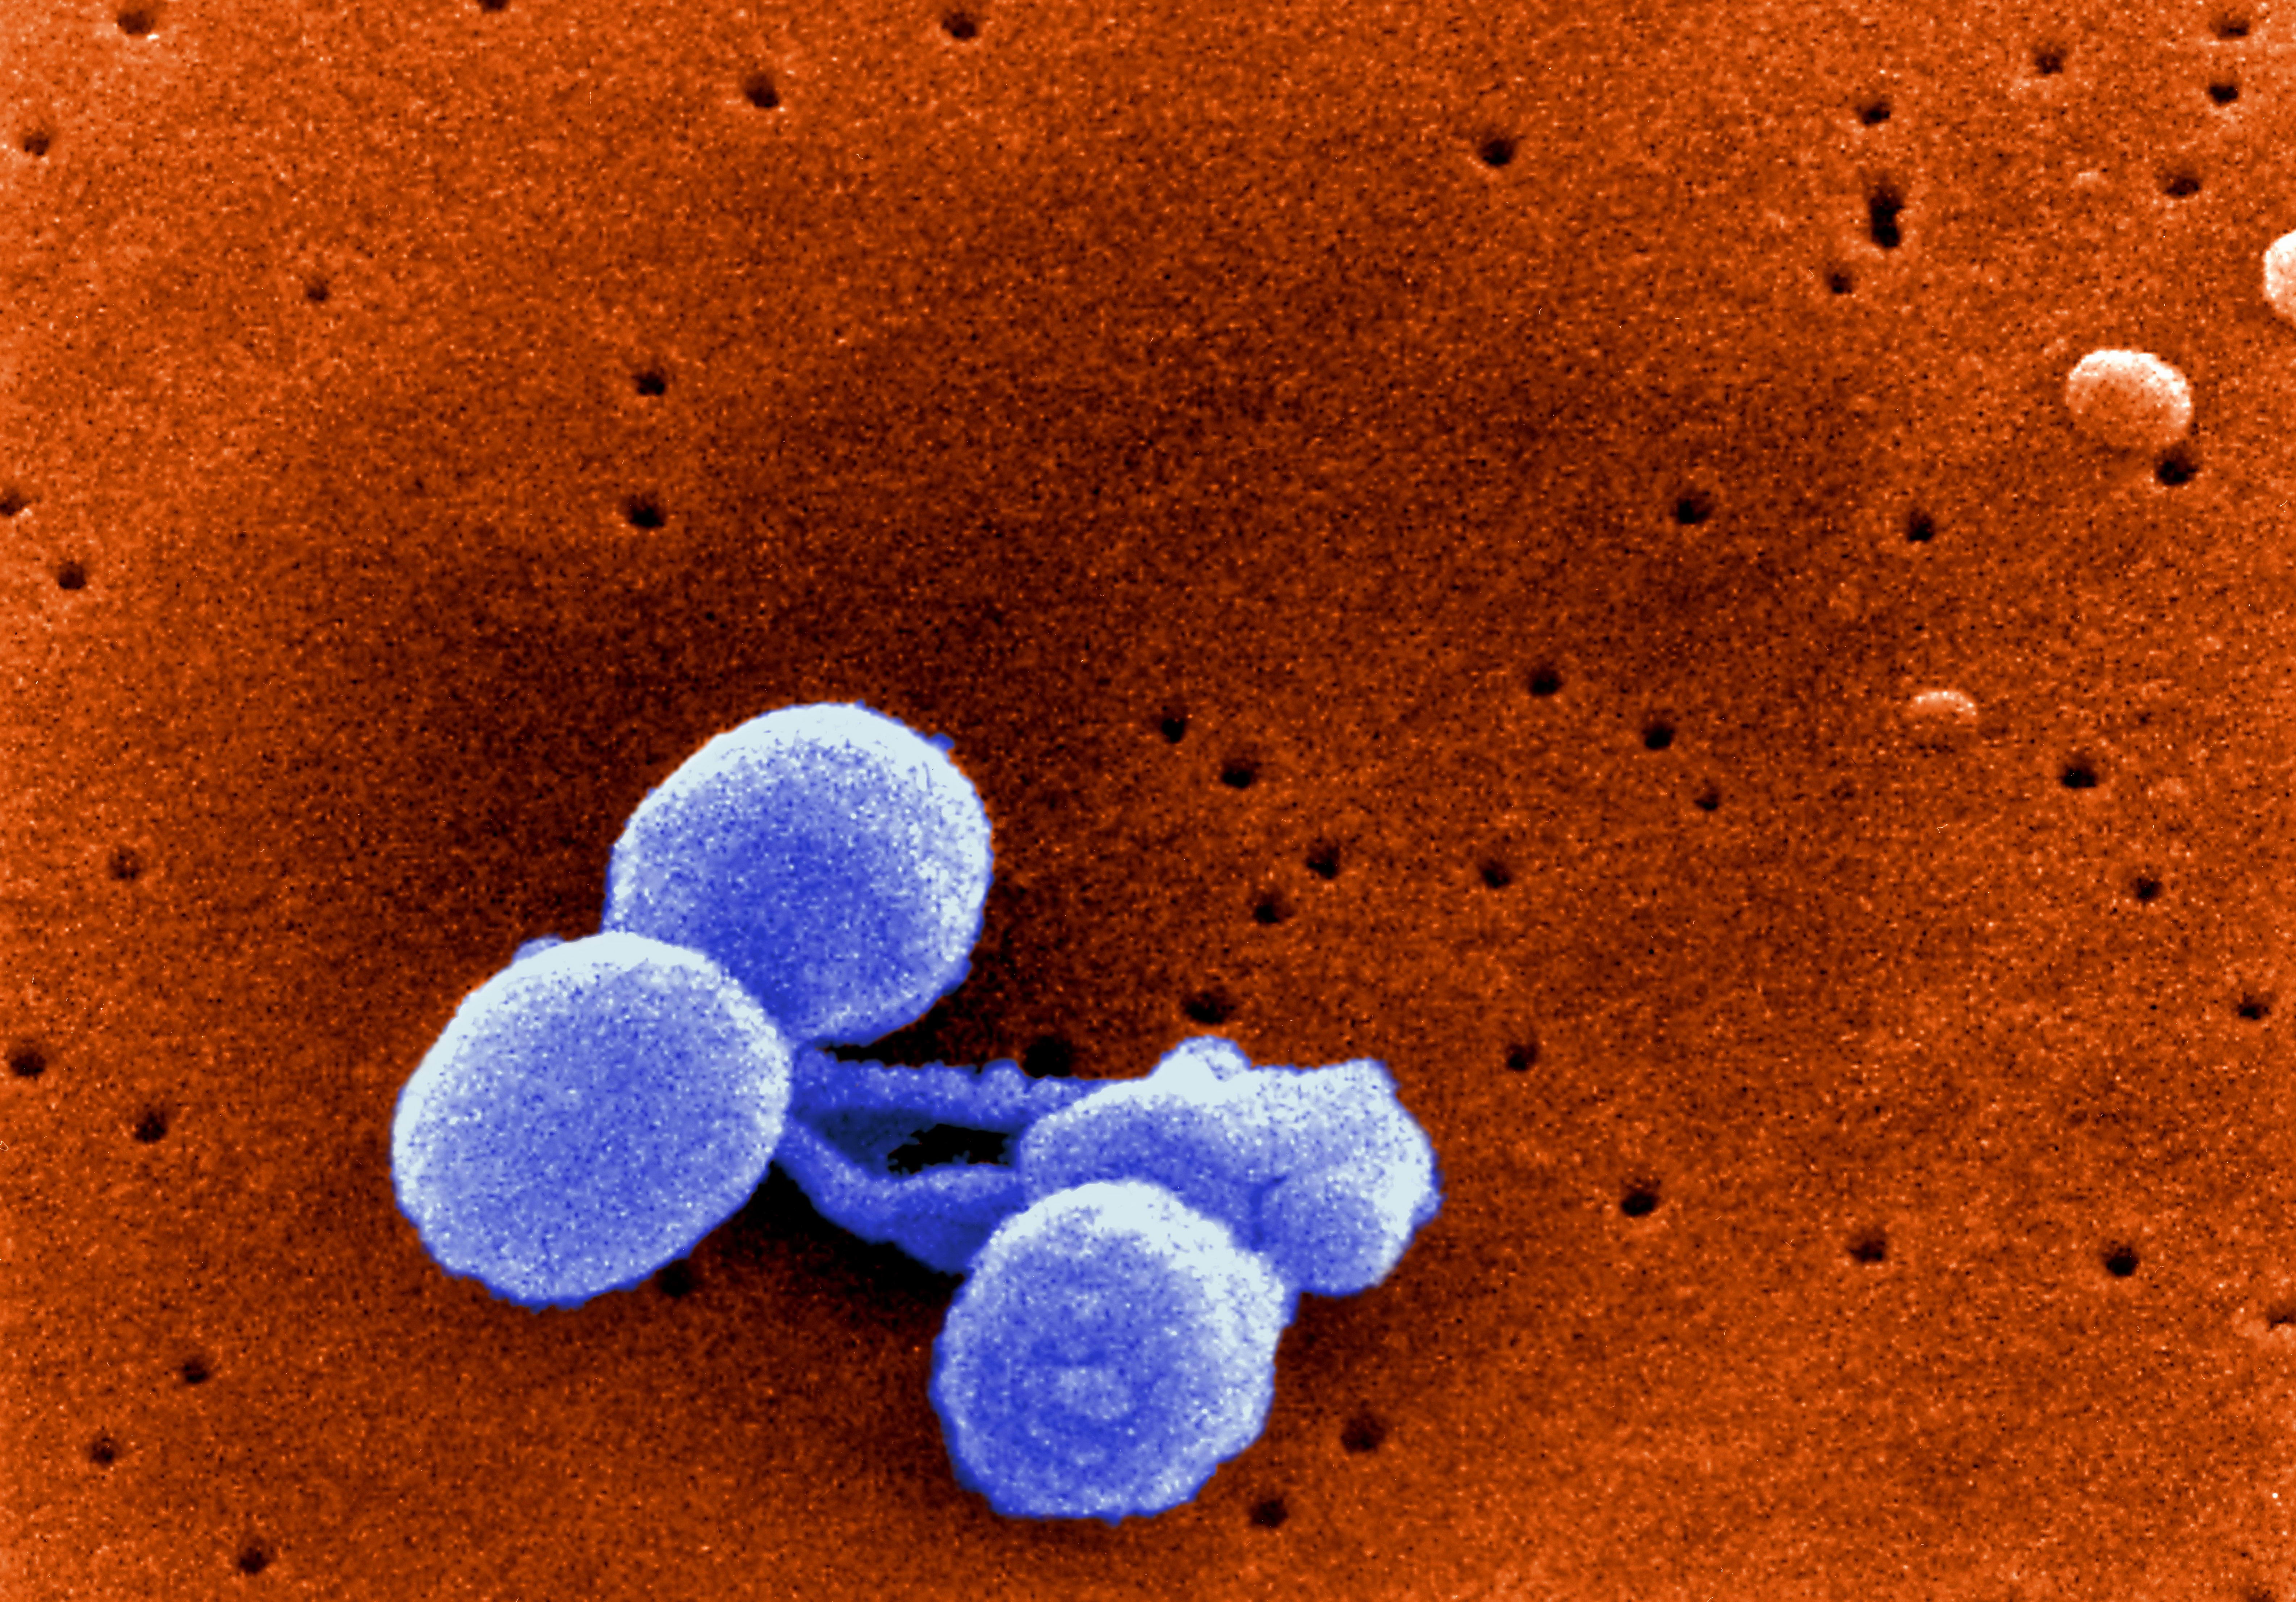

Фотографии бактерий, вызывающих бактериальные пневмонии у животных

Раздел: Другие животные